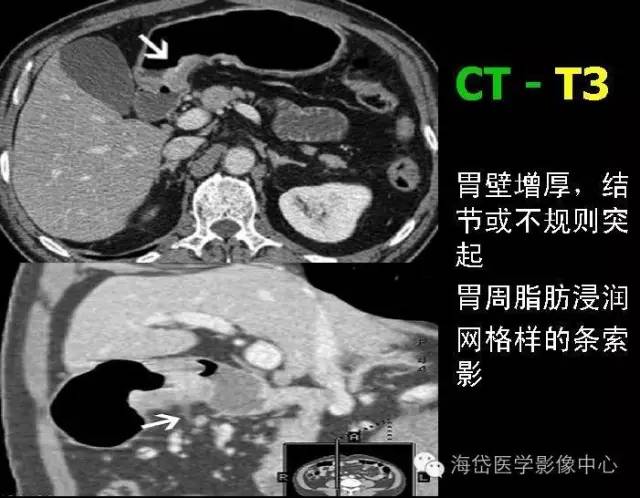

T3 腫瘤侵及漿膜下層。

T2:胃壁增厚,低密度帶中斷,外輪廓光滑,周圍脂肪層清晰條索影少于1/3